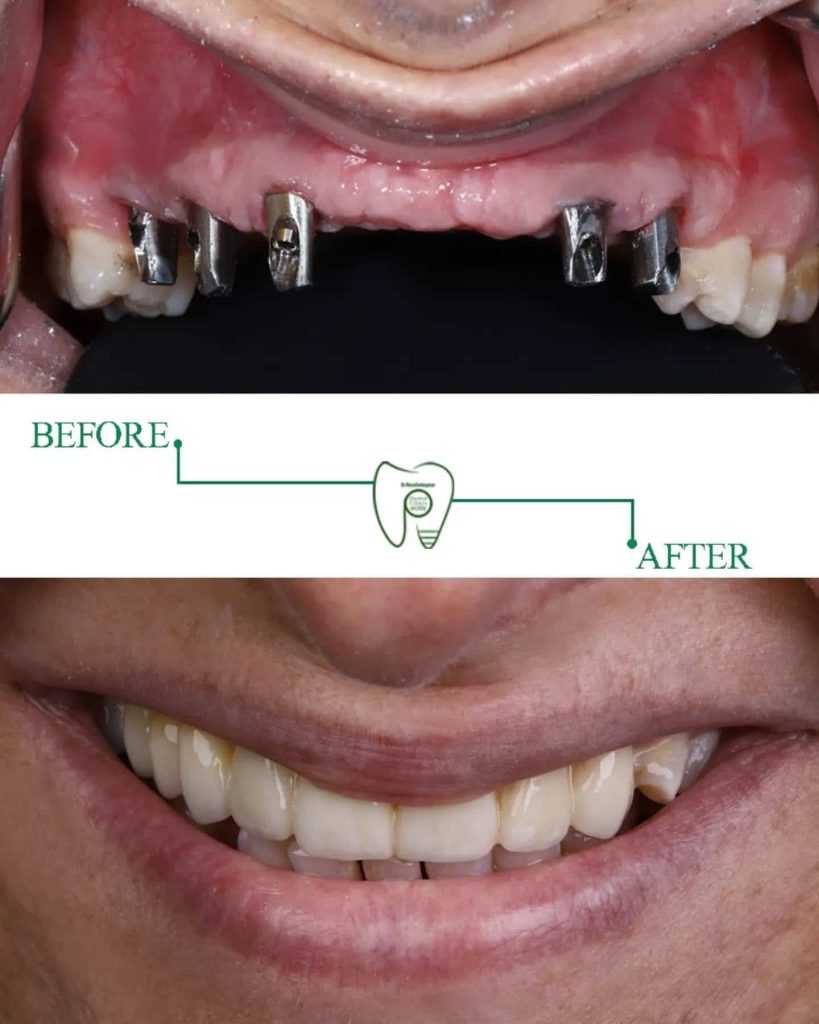

ایمپلنت دندان یکی از پیشرفتهترین و پایدارترین روشهای جایگزینی دندانهای از دست رفته است. برخلاف دندان مصنوعی که ممکن است حرکت کند و باعث ناراحتی بیمار شود، ایمپلنت دقیقاً مانند ریشه طبیعی دندان در استخوان فک جای میگیرد و استحکام و پایداری فوقالعادهای دارد.

مزایای ایمپلنت شامل بهبود قدرت جویدن، حفظ ساختار استخوان فک، جلوگیری از تحلیل لثه و بازگرداندن ظاهر طبیعی دندان است. ایمپلنت همچنین اعتماد به نفس فرد را بالا میبرد، زیرا دیگر نیازی به پنهان کردن لبخند یا ترس از افتادن دندان مصنوعی وجود ندارد.

ایمپلنت فوری در شیراز یکی از محبوبترین روشهای جایگزینی دندان است، زیرا در کوتاهترین زمان ممکن نتیجهای قابل مشاهده ارائه میدهد. برخلاف روشهای سنتی که نیاز به چند ماه انتظار دارند، ایمپلنت فوری به بیمار امکان میدهد در همان روز یا حداکثر چند روز پس از کاشت، دندان موقت داشته باشد.

مزایای ایمپلنت فوری شامل کاهش تعداد جلسات درمان، کمتر شدن درد و تورم، و بازگرداندن سریع ظاهر طبیعی دندان است. این روش برای افرادی که به سرعت نیاز به جایگزینی دندان دارند یا از مسائل زیبایی اهمیت میدهند، ایدهآل است.

ایمپلنت فوری و ایمپلنت معمولی هر دو مزایای خود را دارند، اما تفاوت اصلی در سرعت و راحتی درمان است. ایمپلنت فوری برای کسانی که زمان محدودی دارند یا میخواهند ظاهر دندانشان سریع بازگردد مناسب است، در حالی که ایمپلنت سنتی ممکن است نیاز به چند ماه زمان داشته باشد.